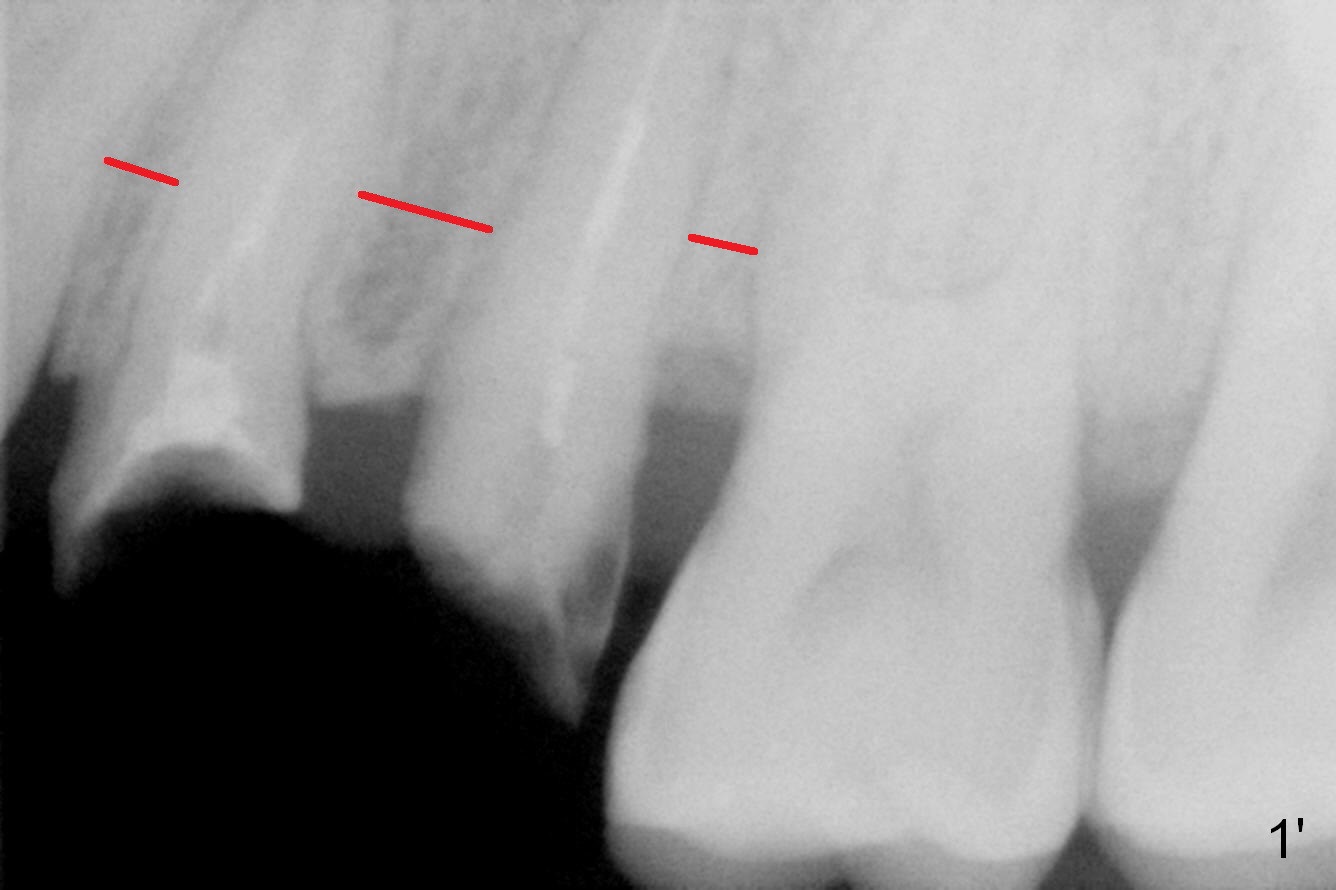

Taking 2 additional PAs with sensor 1 is frustrating (Fig.1,2), no apices shown.

Closer look shows that the width of the interradicular bone is not equal (Fig.1': red line).